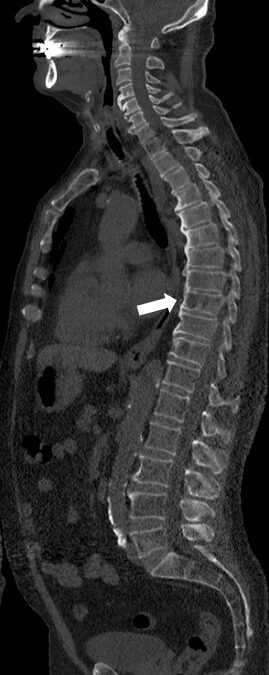

Very low-dose CT examinations can be achieved with low kV and tin filtering, reaching a total dose of 1.5 mSv for this whole-body examination. CT can now become a routine tool to detect and follow-up osteolytic lesions with a benefit of time and simplicity as compared to radiographs and MRI.

• Whole-body low-dose CT can be performed with a median dose of 1.5 mSv.